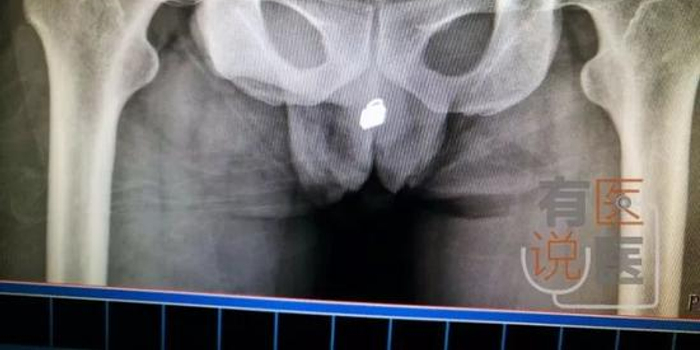

小伙将20cm数据线塞进尿道 称看视频寻刺激(图)

吸毒男子把锁头从尿道塞进膀胱 医生拍片后吓一跳-五花八门-猫扑大杂烩-猫扑网